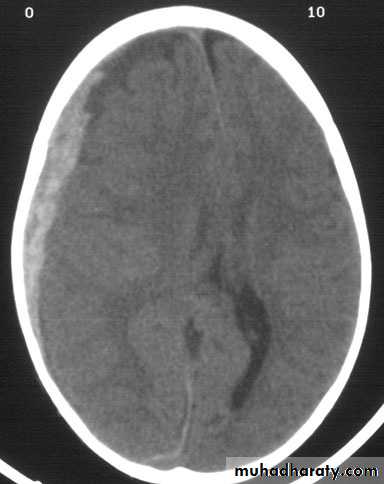

3) Chronic subdural hematoma:

Very common in elderly people by a minor trauma, certain brain tumors,idiopathic hypertension or decreased coagulability.

The patient usually complains of headache, apathy, personality changes, and

can be easily missed as dementia.

Diagnosis: CT scan which shows crescent shape hypodense lesion in the

subdural space.

Treatment: usually burr holes.